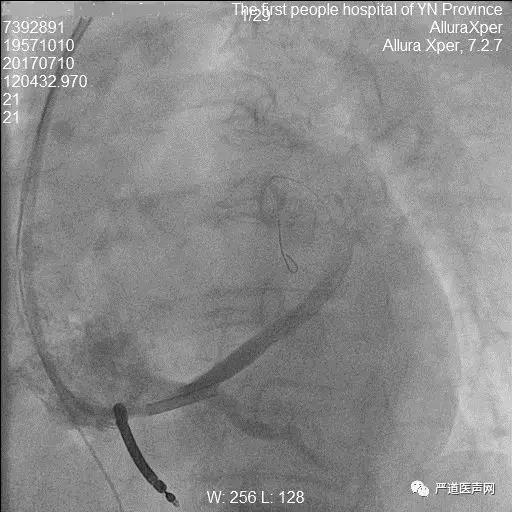

18.jpg

冠状动脉造影显示冠状窦

19.jpg

长鞘进入真腔